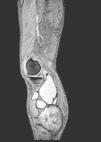

Fig. 3.

MR. Axial and coronal T1-weighted images. Well circumscribed mass (arrows). Increased intensity signal compatible with a subacute presence of blood products.